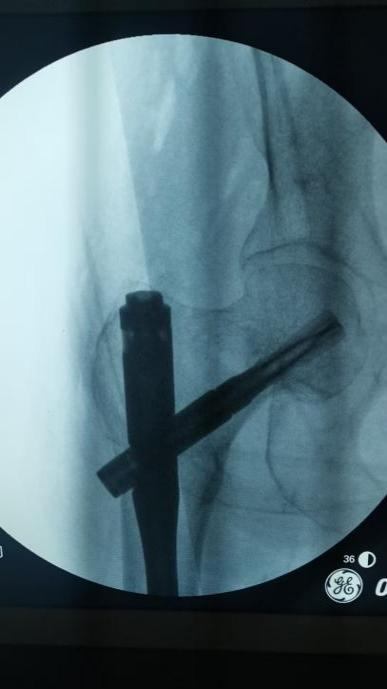

骨科团队迅速评估病情,认为手术治疗是让老人重新站起来的唯一希望,也是降低长期卧床并发症风险的最佳选择。在科主任李忠教授带领下,唐炼副主任医师团队反复研究影像资料,精心设计创伤小、固定可靠的手术方案——微创闭合复位股骨近端防旋髓内钉(PFNA)内固定术。手术仅用时30分钟顺利完成。